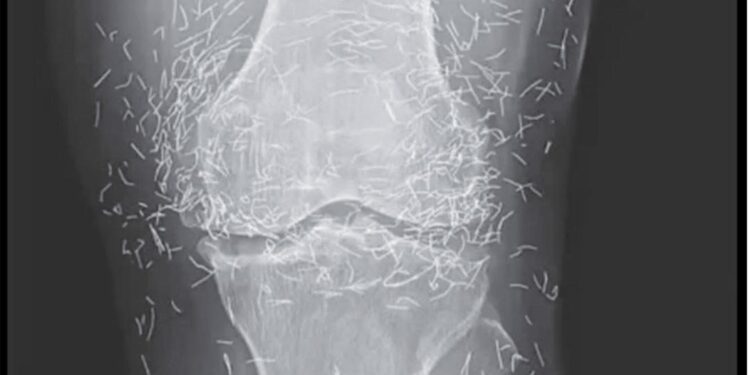

Während der Sitzungen wurden dieser Patientin Goldnadeln um ihre schmerzenden Gelenke eingeführt. Im Gegensatz zur herkömmlichen Methode, bei der sie nach der Sitzung entfernt werden, blieben diese Mikronadeln im Gewebe. Das Ziel? Die wohltuende Wirkung der Stimulation langfristig zu erhalten.

Diese Technik, die manchmal auch als „permanente Akupunktur “ bezeichnet wird, wird in einigen asiatischen Ländern noch immer praktiziert, insbesondere zur Linderung chronischer Schmerzen. Dabei werden winzige sterile Drähte aus Gold oder chirurgischem Stahl eingeführt , die an Ort und Stelle bleiben – manchmal jahrelang oder sogar ein Leben lang.

Bei einer routinemäßigen Röntgenuntersuchung entdeckten die Ärzte zu ihrer Überraschung Hunderte kleiner, glänzender Nadeln, die um seine Knie verstreut waren. Eine wahre medizinische Kuriosität, die sowohl Erstaunen als auch Vorsicht weckte. Denn obwohl Gold ein inertes und gut verträgliches Metall ist, ist die längere Anwesenheit von Fremdkörpern im Körper nie ungefährlich.

Laut Experten für medizinische Bildgebung können diese Nadeln bestimmte Körperbereiche auf Röntgenbildern verdecken und so die Diagnose anderer Probleme erschweren. Vor allem erschweren sie die MRT-Untersuchung erheblich: Es besteht die reale Gefahr, dass sich die Nadeln unter dem Einfluss des Magnetfelds bewegen und empfindliches Gewebe schädigen.